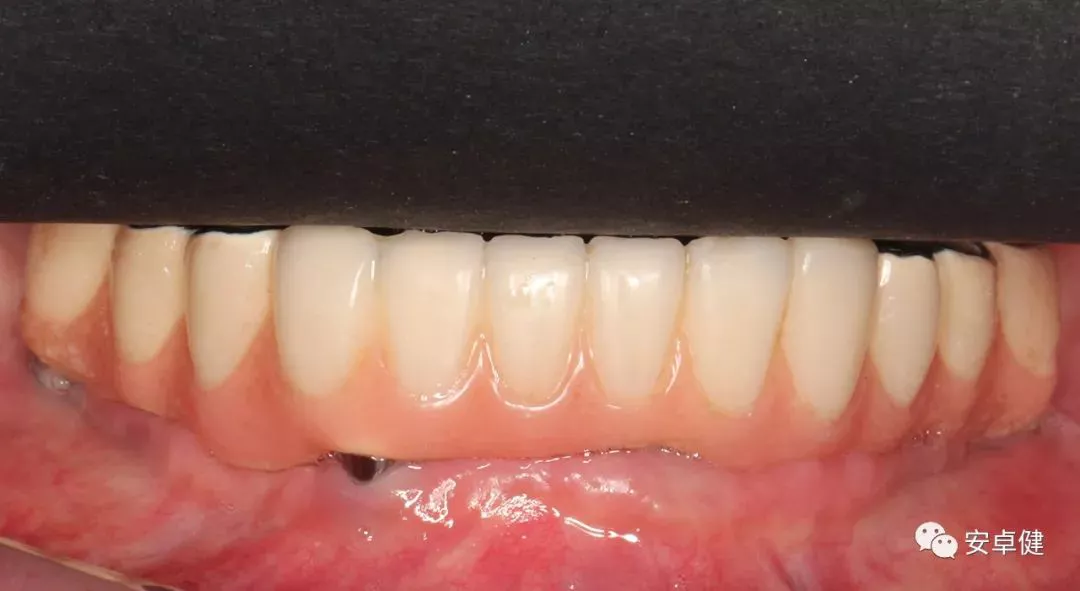

戴最终修复体正面咬合照

戴牙后8个月复诊正面咬合照

• 随访可见患者口腔卫生状况可,牙龈无红肿;

• 下颌修复体状态良好,无修复体机械并发症;

• 种植体基台稳定性良好,无松动;

• 种植体无松动,周围无红肿、溢脓及疼痛表现;

• 正中、前伸及侧方咬合检查可见咬合印记分布均匀,咬合关系良好;

• 患者反映日常使用良好,舒适性佳,满意度高。